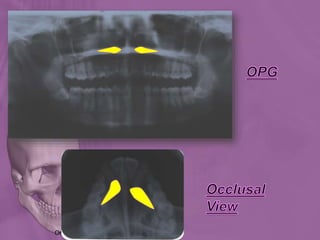

The 4 Diagnostic regions in OPG

Dentoalveolar

region

Maxillary regionMandibular region

TMJ, including retromaxillary